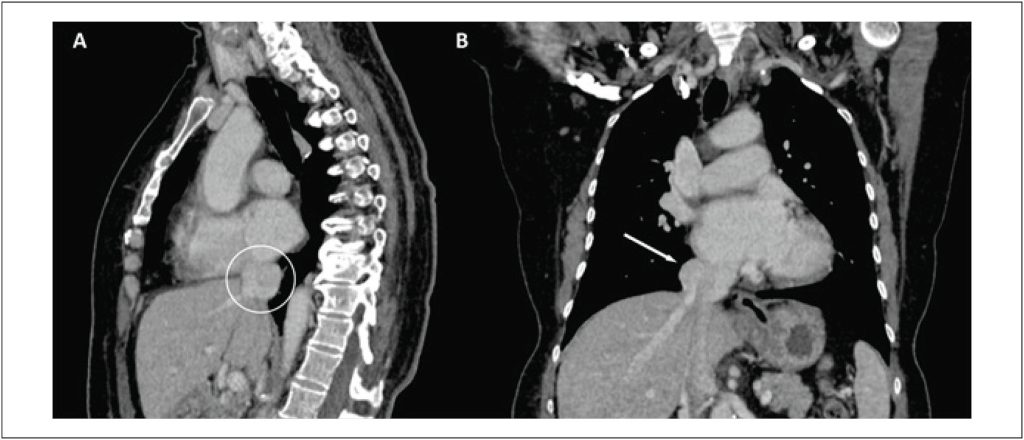

Aneurysm of the Suprahepatic Inferior Vena Cava: A Case Report

Aneurysms of the inferior vena cava (IVC) are a rare occurrence in the cardiovascular system and can present with a variety of signs and symptoms. In many cases, patients remain asymptomatic, which makes diagnosis difficult. Venous aneurysms are defined as an abnormal and persistent dilation of a vein in a specific area, with a diameter at least twice that considered normal. An IVC aneurysm is a specific type of venous aneurysm. This case report is relevant because this condition is rare; by 2021, only around 70 cases had been described in literature.